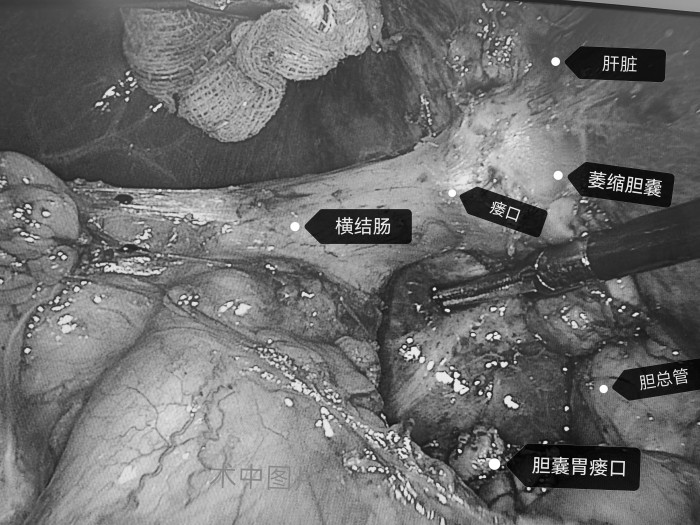

沈紅波為柴女士制定治療方案,行腹腔鏡下膽囊切除術(shù)。術(shù)中見(jiàn)膽囊明顯萎縮,與橫結(jié)腸、胃壁致密粘連,已形成膽囊胃瘺、膽囊結(jié)腸瘺。沈紅波分別修補(bǔ)兩個(gè)瘺口,并切除萎縮的膽囊。